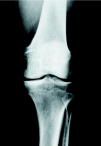

Figura 2. Genu varo artrósico en un varón de 47 años con afectación moderada del compartimento interno.

Figura 3. Corrección quirúrgica del caso mostrado en la figura 2. Se utilizó la placa T3, que proporcionó un montaje estable después de la osteotomía, añadiéndose un tornillo de compresión para mayor solidez. La corrección fue de 8o de valgo; la consolidación se obtuvo a las 9 semanas. La imagen corresponde al control a los tres años.